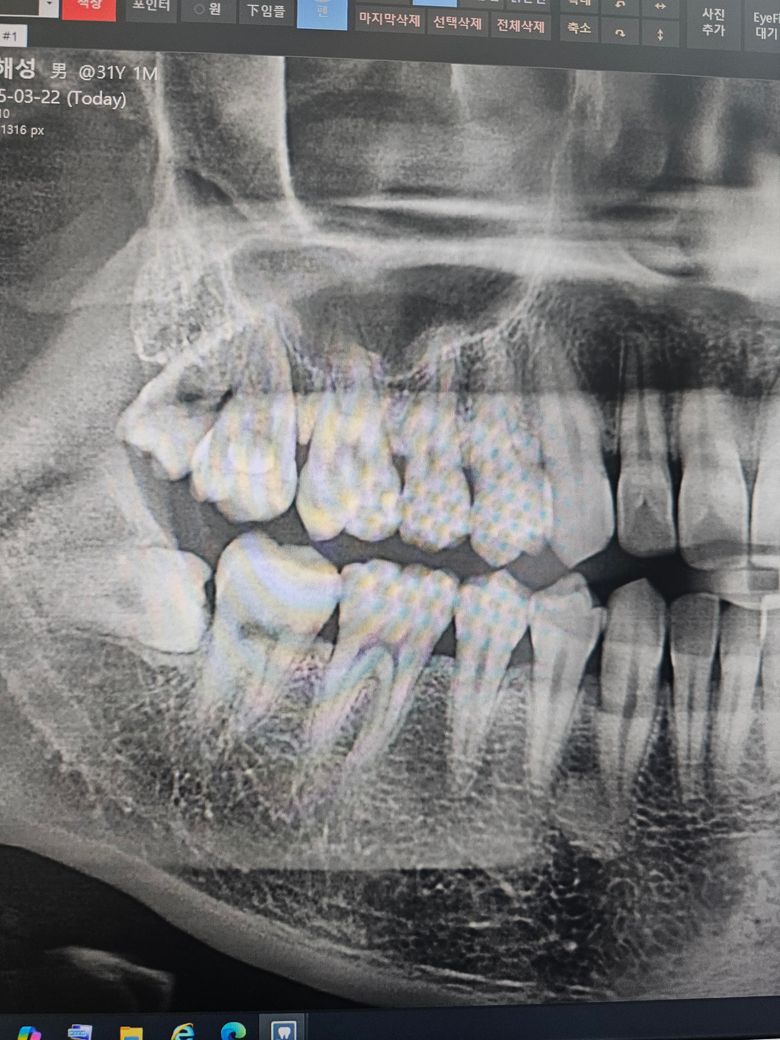

인접면충치 전문가분들의 의견이 궁금합니다

크라운5개+인레이4개(4개중3개는 크라운권장)+레진+잇몸치료+윗쪽 왼쪽 사랑니 발치

대부분 레진 인레이(그중 하나는 크라운할수도) +잇몸치료+사랑니발치

첫번째병원에선 즉 크라운7~8개를 하라고하셨는데 내이빨을 너무 많이 갈아내야 하는게 아닌가... 싶고

두번째병원에선 의사마다 견해와 처방이 다르다 이전병원은 충치인지 아닌지 약간만 의심되도 일단 갈아내고 없애야한다는 판단인거같다고 말씀하셨고 두번째병원에서는 인접면충치가 확인하기 힘들 뿐더러 갈아냈는데 충치가 아닐수도있다~ 라고 애매모호하게 말씀하셨어요

• 1번 째 사진